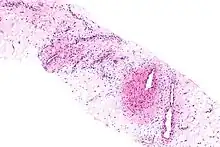

Micrograph of an aggressive angiomyxoma. Core biopsy. H&E stain.

Microscopy

• Vascular appearance of tumor[7]

• Hypocellular mesenchymal lesion

• Spindled and stellate cells with an ill-defined cytoplasm

• Cells loosely scattered in a myxoid stroma

• No evidence of nuclear atypia and mitosis

• Numerous, thin-to-thick wall vessels of different sizes

• Myxoid, hypocellular background

• Bland cytological appearance of spindle cells